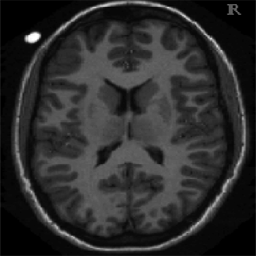

In Figure 1.1 the influence of the choice of a constant in (1.1) is shown, over-regularising the reconstructed image if chosen too small and under-regularising if chosen too large. Moreover, in Figure 1.2 the reconstructed images with constant and spatially-dependent are shown, where has been optimized with the bilevel approach for (1.1) proposed in [9].

4.1. Uniform Gaussian noise

In this first experiment, we consider the denoising problem with brain scan images. The first set consists of images of pixels and Gaussian noise with zero mean and variance . The original and noisy images are shown in Figure 4.1. The domain decomposition-semismooth Newton algorithms run with the parameter values , , and . The results are shown in Figure 4.2. From the surface representation of , we can observe that is continuous and its shape is related to the one of the original image. In particular, the regularization is stronger in homogeneous regions in the image, and weaker where the image intensity undergoes variations on a smaller scale.